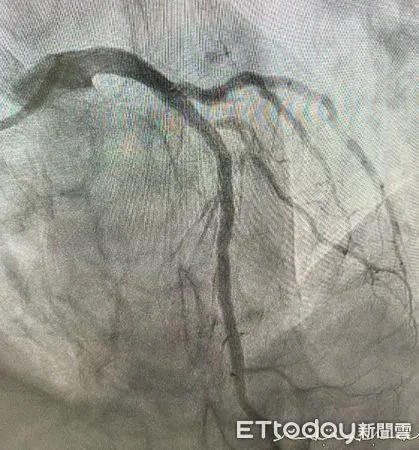

果然在心導管檢查後,顯示其冠狀動脈左前降支中段出現高達90%的嚴重狹窄,當日即施行血管擴張與支架置放手術,術後馬先生症狀明顯緩解,成功避免了可能發生的重大心血管事件。